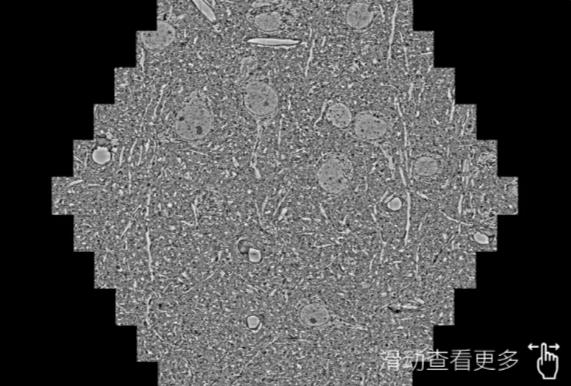

鼠脑切片。左图使用漯河蔡司漯河扫描电镜MultiSEM706对165μmx143pm面积区域成像,耗时仅需1.5秒。右图为鼠脑切片中30μm区域放大效果。样品由芝加哥大学B.Kasthuri提供。

使用蔡司高速漯河扫描电镜MultiSEM对1mm²人脑皮层组织进行高分辨成像,并对其中的各种细胞结构进行三维重构分析。左图展示了2x3mm²组织平面中锥体神经元的三维重构效果。右图显示了局部体积神经元三维重构。图像由哈佛大学chtman实验室提供,渲染图由D. Berger 制作。